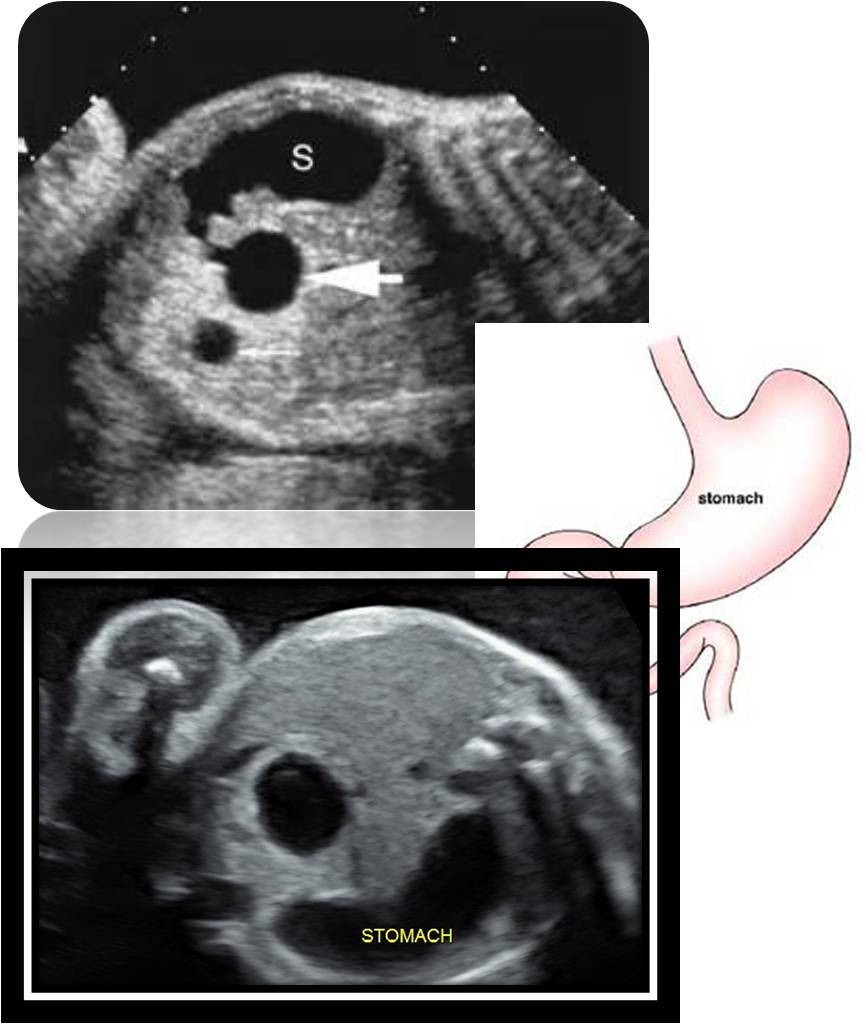

Duodenal atresia

congenital absence or complete closure of a portion of the lumen of theduodenum